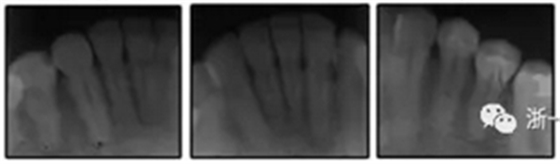

患者是一名39歲的白人婦女,病史不明。她主訴是她的右側(cè)顳下關(guān)節(jié)有不適癥狀,并希望改善她的笑容。她有一個(gè)對(duì)稱的臉型和一個(gè)II類2分類的微笑。她的側(cè)貌是凸的,90°的鼻唇角和骨性下頜骨發(fā)育不足??趦?nèi),上頜中線與面部重合,但下頜中線向右側(cè)偏移5mm;存在6mm的深覆蓋。她的兩側(cè)都是I類磨牙關(guān)系,左側(cè)是I類尖牙關(guān)系,右側(cè)是完全的II類尖牙關(guān)系。下頜右側(cè)第二前磨牙先天性缺失(圖1和圖2)。最初的全景片顯示了足夠的骨質(zhì)水平和全部的第三磨牙(圖3)。治療前的頭影測(cè)量片片和相應(yīng)的頭影測(cè)量圖(圖3)證實(shí)ANB為7°,Wits評(píng)估為6 mm的骨性II類錯(cuò)合(表)。上頜切牙相對(duì)與面部和顱底的位置很好。下頜切牙前傾。診斷為II類2分類錯(cuò)合畸形,伴有骨性下頜發(fā)育不足,右側(cè)顳下頜關(guān)節(jié)癥狀,下頜中線向右側(cè)偏移5mm,先天性右下第二前磨牙缺失。

圖3. 治療前頭影側(cè)位片,頭影測(cè)量描跡圖和全口X光片

患者決定采用非手術(shù)治療方法,側(cè)貌沒(méi)有任何預(yù)期的變化。治療后面部照片(圖5)顯示她改善的微笑和側(cè)貌,包括尖牙保護(hù)合。由于先天性第一前磨牙缺失,右磨牙關(guān)系為III類。治療后牙齒石膏模型(圖6)顯示實(shí)體牙齒交錯(cuò)排列情況,并且全景X線片顯示可接受的牙根平行度而且沒(méi)有牙根吸收表現(xiàn)(圖7)。最終的頭影測(cè)量片(圖7)證實(shí)了面部評(píng)估,并且描跡圖顯示深覆蓋的改善,同時(shí)保持上頜切牙位置并通過(guò)測(cè)量ANB角度和Wits評(píng)估改善骨性II級(jí)關(guān)系(表)。治療前后的疊加圖顯示由于下頜切牙前傾的增加改善了下唇平衡(圖8)。如相關(guān)治療計(jì)劃所預(yù)測(cè)的那樣,B點(diǎn)出現(xiàn)。A進(jìn)行牙科錐形束計(jì)算機(jī)斷層掃描以記錄下頜前牙區(qū)的骨質(zhì)變化。如預(yù)期的那樣,由于治療導(dǎo)致該區(qū)域的骨量增加(圖9)。